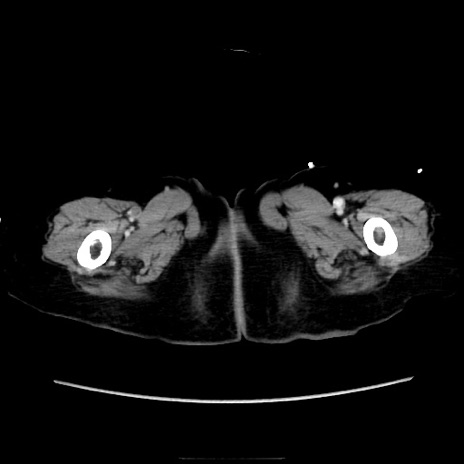

症例40(横断像)

横断像